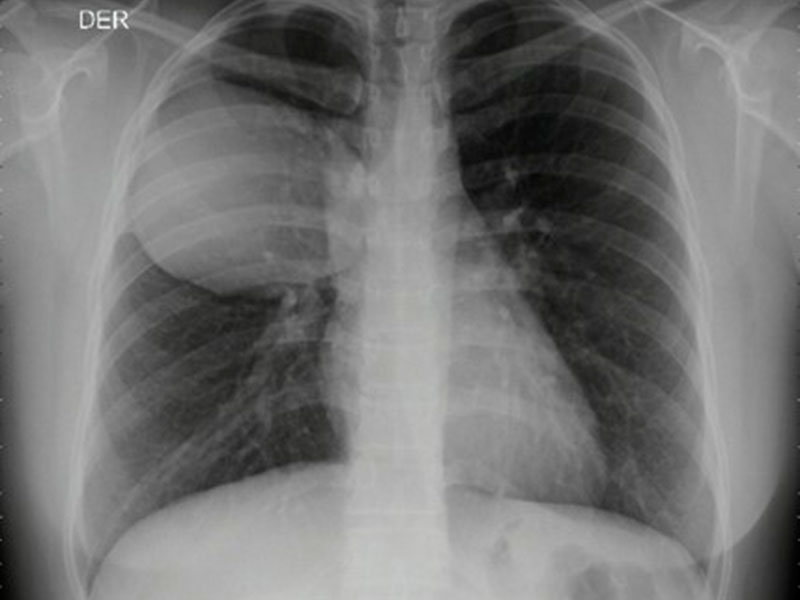

Quiste Hidatídico

Es una enfermedad parasitaria humana causada por el estado quístico del parásito Echinococcus granulosas, el cual infecta el intestino de los perros, su huésped definitivo. El humano sirve como huésped incidental por ingestión de huevos en vegetales o agua contaminada con las heces del perro.